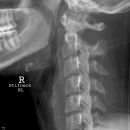

Densfraktur